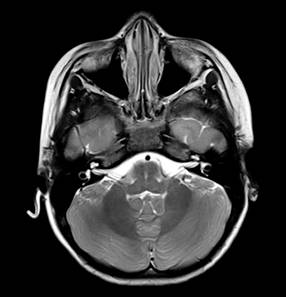

Se trata de paciente femenino de cinco años de edad que ingresa al Servicio de Urgencias en el Hospital Angeles México con signos vitales en parámetros normales, presenta mioclonías focalizadas en miembro torácico derecho, emesis, atetosis y relajación de esfínteres. En urgencias presenta nuevamente crisis focalizadas en el miembro torácico derecho. En hospitalización persiste con crisis convulsivas refractarias a tratamiento. Se realizan paraclínicos (hemocultivo y hemograma) y se recaba electroencefalograma (EEG) y resonancia magnética (RM), la cual muestra cambios morfológicos, leucoaraiosis (Figura 1) y alteraciones vasculares (Figura 2). Posteriormente, se realiza punción lumbar con presencia de anticuerpos anti-NMDA y tomografía por emisión de positrones y tomografía computarizada que muestra hipometabolismo severo en sistema nervioso central. Ingresa a UTIP para sedoanalgesia, plasmaféresis y aplicación de inmunoglobulina intravenosa e inmunomoduladores.